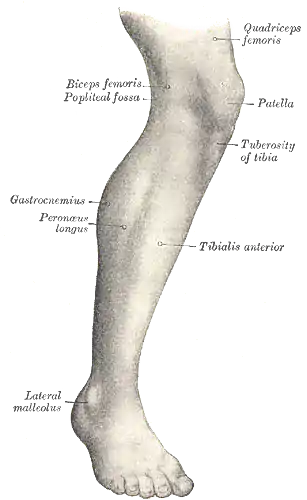

Lateral aspect of right leg Muscles of Leg (lateral view, deep dissection)

Muscles of Leg (lateral view, deep dissection)